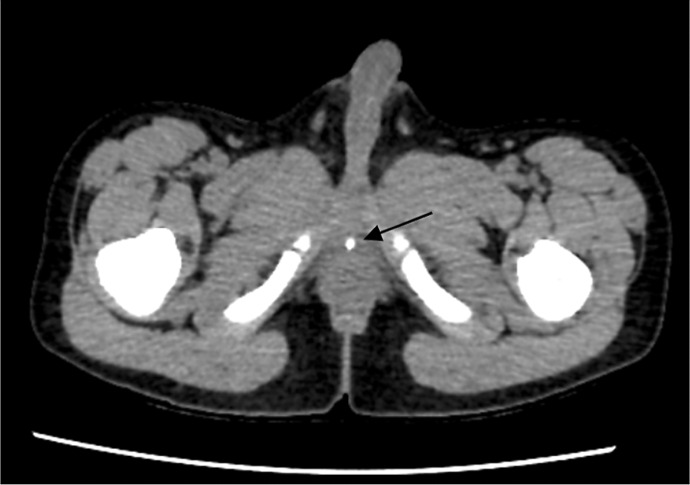

Case presentation: We present a case of intermittent urinary retention resulting from a stone obstructing the PUV. The patient experienced intermittent urinary retention for over a month. A computed tomography scan revealed a bladder stone in the posterior urethra. The intracorporeal lithotripsy for calculus with fulguration of the PUV was performed using holmium:YAG laser.